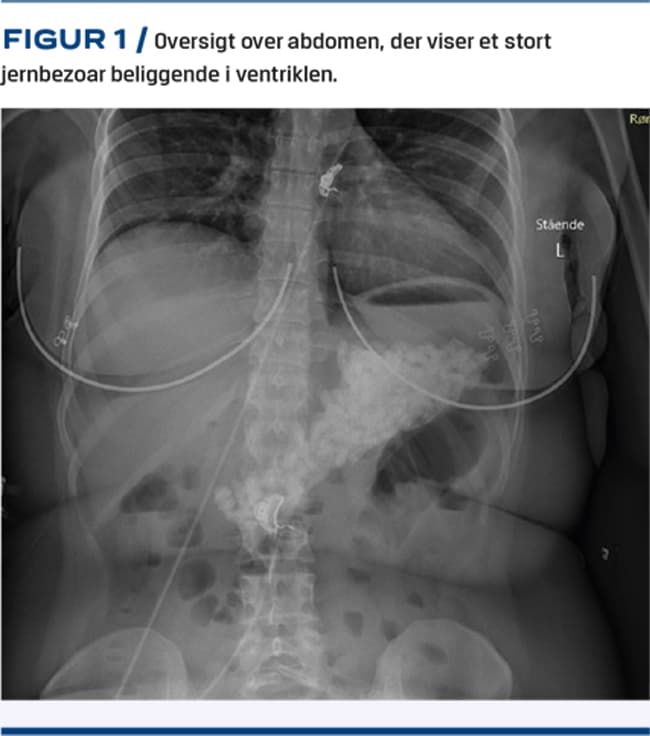

En kvinde i 20’erne blev indlagt tre timer efter i suicidalt øjemed at have indtaget 300 stk. jern C-tabletter (indeholder 330 mg ferrofumarat = 100 mg elementært jern), hvilket svarer til en jerndosis på 400 mg/kg. Ved indlæggelsen var patienten uden somatiske symptomer og P-jernniveauet blev målt til 82 µmol/l. En oversigt over abdomen (OOA) viste store mængder jerntabletter i ventriklen (Figur 1), og der blev påbegyndt behandling med antidoten deferoxaminmesilat samt udført gastroskopi i forsøg på dekontaminering. Man fandt en ødematøs slimhinde og et stort bezoar bestående af en tyk masse af føderester og delvist opløste jerntabletter, hvoraf hovedparten blev udhentet. P-jernniveauet faldt herefter til 49 µmol/l. En fornyet OOA viste resterende jerntabletter i ventriklen og spredt i tyndtarmen, hvorfor der blev udført regastroskopi med evakuering af restbezoaret. Behandling med macrogollaksantia blev initieret (en såkaldt »tarmskylning«) for at fremskynde tarmtømningen pga. jerntabletterne i tyndtarmen. Pga. betydelig perforationsrisiko blev patienten overflyttet til klinisk observation på en intensivafdeling på et højtspecialiseret hospital. Her fortsatte man med tarmskylning i to døgn, hvorefter patienten blev udskrevet til en psykiatrisk afdeling efter fire døgns indlæggelse. Efterforløbet var uden tegn til komplikationer eller organskader.

Hos svært forgiftede patienter er hurtig risikovurdering og iværksættelse af behandling essentiel, da dødeligheden af intenderede forgiftninger er op til 10% [3]. OOA kan anvendes til verificering af indtag af de røntgenfaste jerntabletter. Patienten i sygehistorien havde indtaget en livstruende mængde jerntabletter, og behandlingen var en kombination af endoskopisk dekontaminering med efterfølgende tarmskylning og intravenøs administration af deferoxamin. Giftlinjens kriterier for påbegyndelse af behandling med deferoxamin er tegn til alvorlige systemiske manifestationer, P-jernniveau > 60 µmol/l og symptomer ud over lette GI-symptomer eller P-jernniveau > 90 µmol/l [2]. Vi valgte at afvige fra disse kriterier og påbegynde tidlig behandling pga. det enorme indtag.

Intentional iron overdoses have an insidious and potentially fatal clinical course. This is a case report of a young woman, who deliberately ingested 300 tablets ferrous fumarate 330 mg, i.e. 400 mg elementary iron per kg body weight. Plain abdominal radiographs showed a conglomerate of iron tablets in the ventricle. Treatment consisted of endoscopic removal of tablets, deferoxamine antidote treatment, and whole bowel irrigation with macrogol laxatives. Toxicological risk evaluation of intentional iron overdoses is necessary to timely effectuate life-saving multidisciplinary empiric treatments.